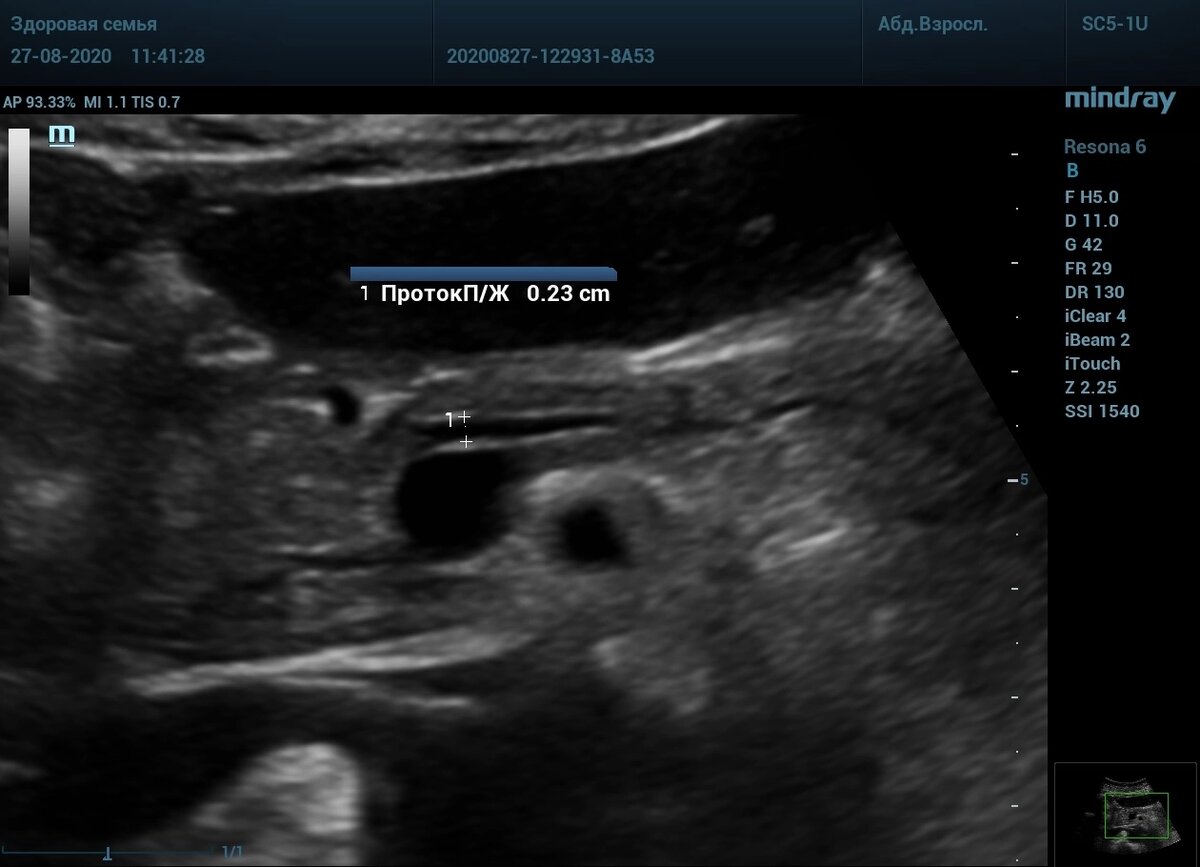

🖼️Признаки хронического панкреатита - множество кальцинатов и расширение панкреатического протока.